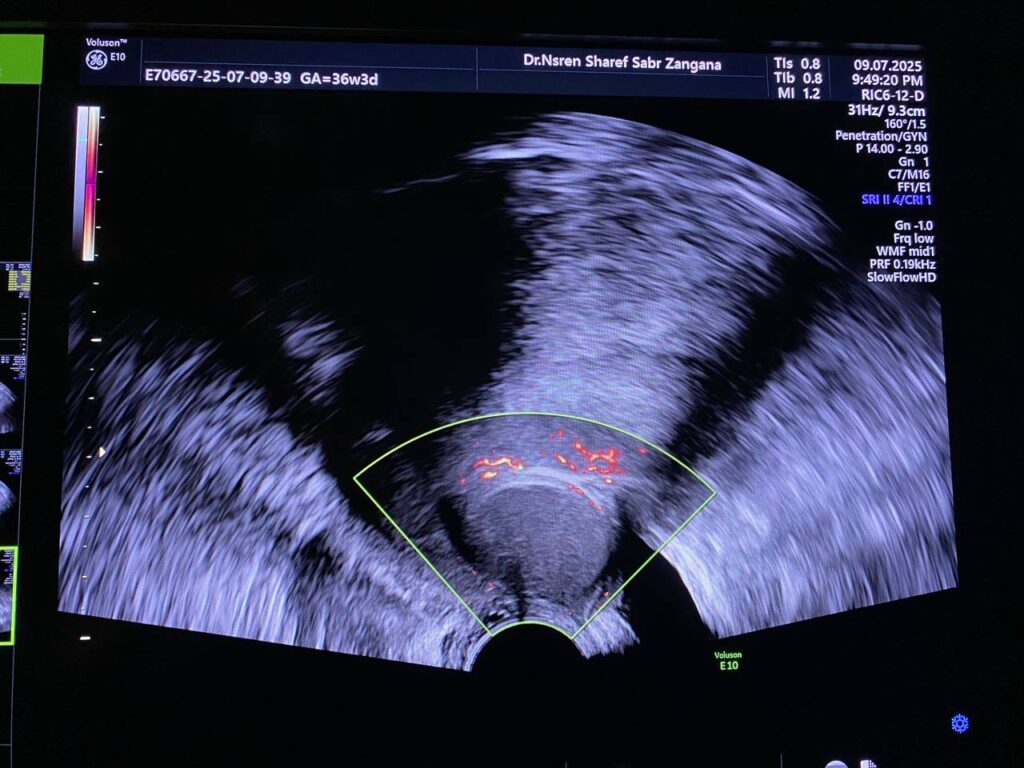

presence of well defined avascular heterogenous cystic mass 26x21mm , between the corpocervical junction and posterior urinary bladder , mostly endometriosis

presence of well defined avascular heterogenous cystic mass 26x21mm , between the corpocervical junction and posterior urinary bladder , mostly endometriosis